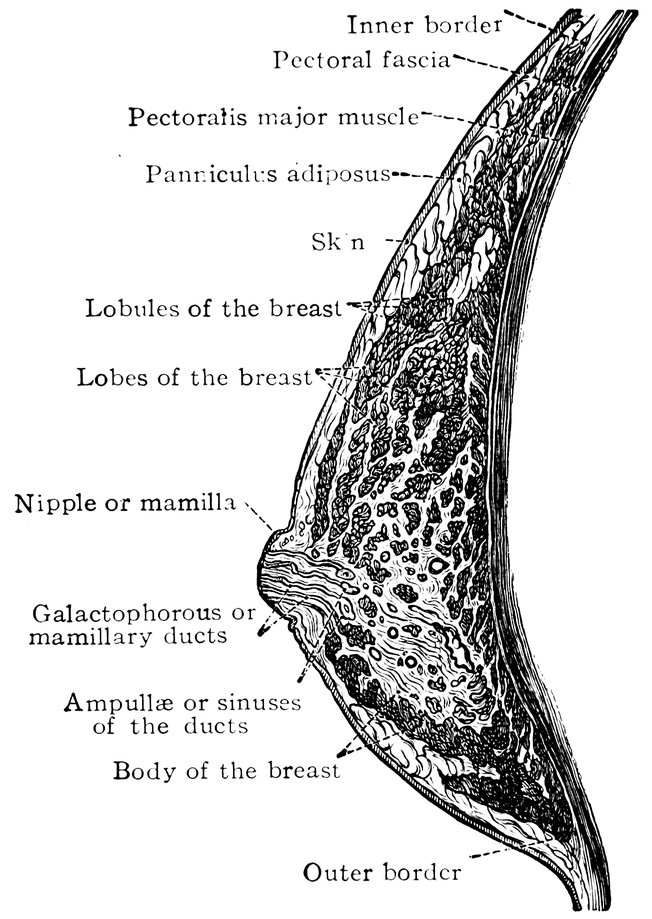

| 47. | Horizontal section through the female breast | 75 |

The beauty of woman, a prominent secondary sexual character, makes its first appearance at puberty, when the girl’s form, hitherto undifferentiated in its external bodily configuration, begins to assume a soft and rounded appearance, when the features become regular, the breasts enlarge, and the pubic hair begins to grow—when, in short, to the primary sexual characters already existing, the secondary sexual characters are superadded.

Feminine beauty continues to increase until the attainment of sexual maturity. In her third decade woman arrives at the acme of her sexual life and at the same time attains the perfection of her beauty.

The ensuing sexual phases, pregnancy, parturition, and lactation, entail a decline in beauty, not rapid indeed, but advancing gradually, with the slow yet sure-footed pace of time. The organic revolutions accompanying these processes leave traces recorded upon the surface of the body in conspicuous and indelible characters. The illnesses, also, which so often accompany the fulfilment of sexual functions, in injuring health impair also beauty.

A woman who has given birth to and nursed an infant begins to lay on fat, and this tendency to obesity becomes more pronounced as the climacteric period approaches. The breasts become inelastic and pendent, the abdomen becomes ungracefully prominent; the tonicity of the entire organism gradually declines, and, in consequence of the loss of elasticity in the subcutaneous cellular tissue, the dreaded wrinkles make their appearance and the features become wizened. Beauty is a thing of the past. With the cessation of the sexual life the external secondary sexual characters disappear, and the old woman is even farther removed than the old man from our conception of beauty.